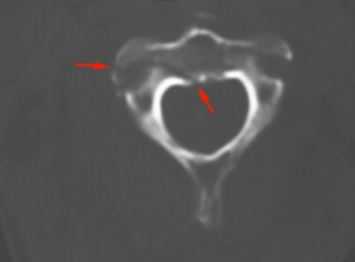

КТ. Перелом тела С2 (красные стрелки).

КТ является методом выбора для оценки костного повреждения. Однако более полную информацию о состоянии спинного мозга даёт МРТ.